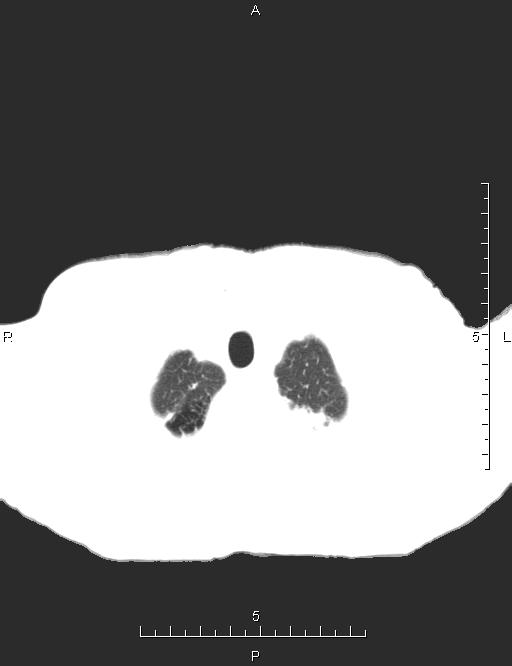

CT51138:胸部CT

男,87岁,咳嗽、咳痰、憋气10余天。

慢支伴左上肺前段感染,纵膈淋巴结肿大,前上纵隔软组织结节影,考虑淋巴结或胸腺瘤

粟粒型肺结核?不排除肺癌多发转移可能

两上肺、右肺中叶可见斑片结节索条影,部分病灶边缘欠清,部分结节位于胸膜下,纵隔内可见多发稍大淋巴结,考虑;:两肺感染性病变,结核可能,建议结合临床,随访复查,排除转移灶。